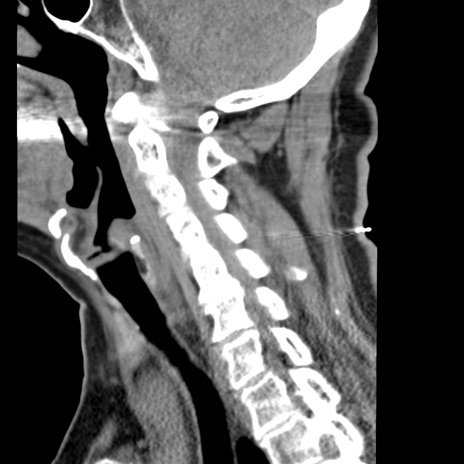

症例50 頚椎CT(矢状断像)

【症例】60歳代女性

【主訴】後頭部〜右後頸部にかけての痛み

【現病歴】本日飲食店でコーヒーを飲んでいたところ、突然後頭部〜右後頸部にかけて痛みが出現し、右上肢の感覚障害を伴ったため救急要請。

【身体所見】脳神経学的に明らかな異常所見を認めず。右上肢に軽度の感覚障害あり。

異常所見と診断は?

頚椎CT